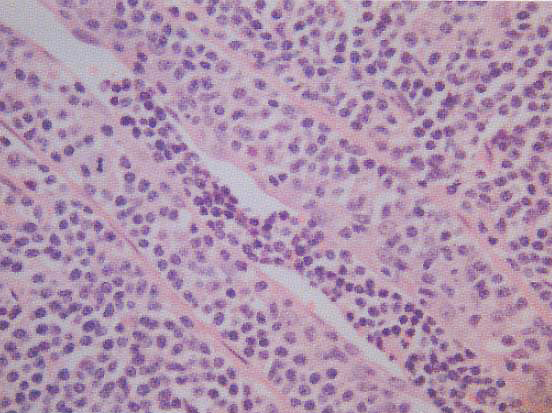

Fig. 3: VATS lung biopsy showing extensive diffuse infiltration by mainly small- to medium-sized slightly atypical lymphoid cells. Bronchial mucosal linings are also infiltrated by lymphoid cells. Immunophenotyping study shows that these lymphoid cells are CD20+, CD3- and CD5-, confirming the diagnosis of extranodal marginal zone B cell lymphoma of the MALT type.